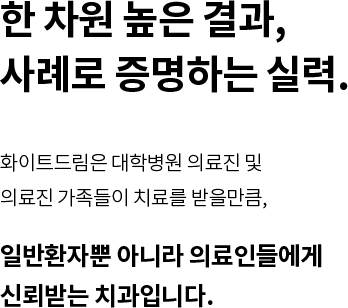

자연치아 보존원칙

고난이도케이스 치료

임플란트